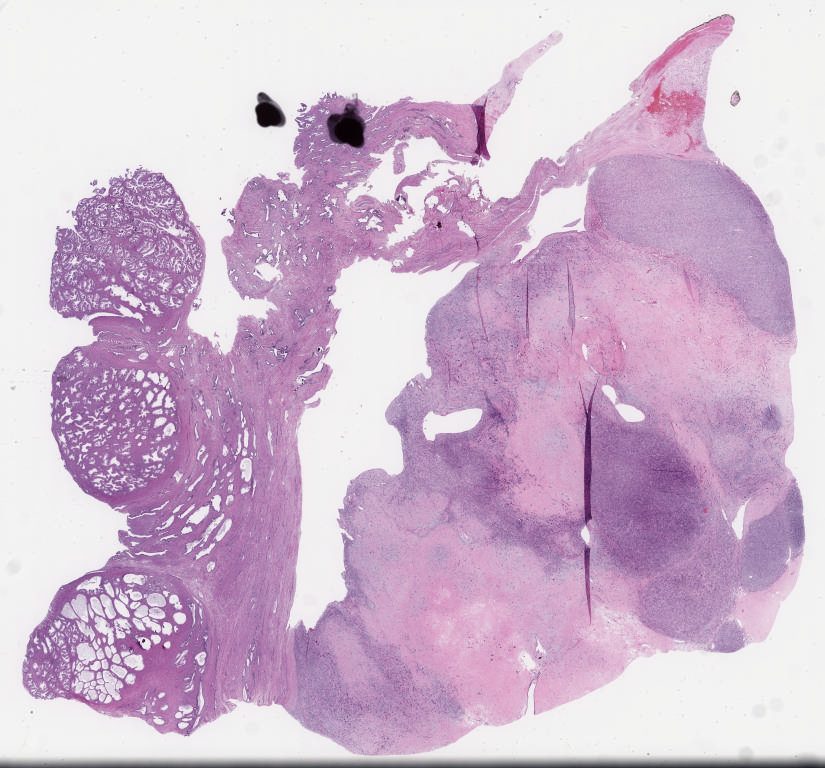

797774.svs

40X